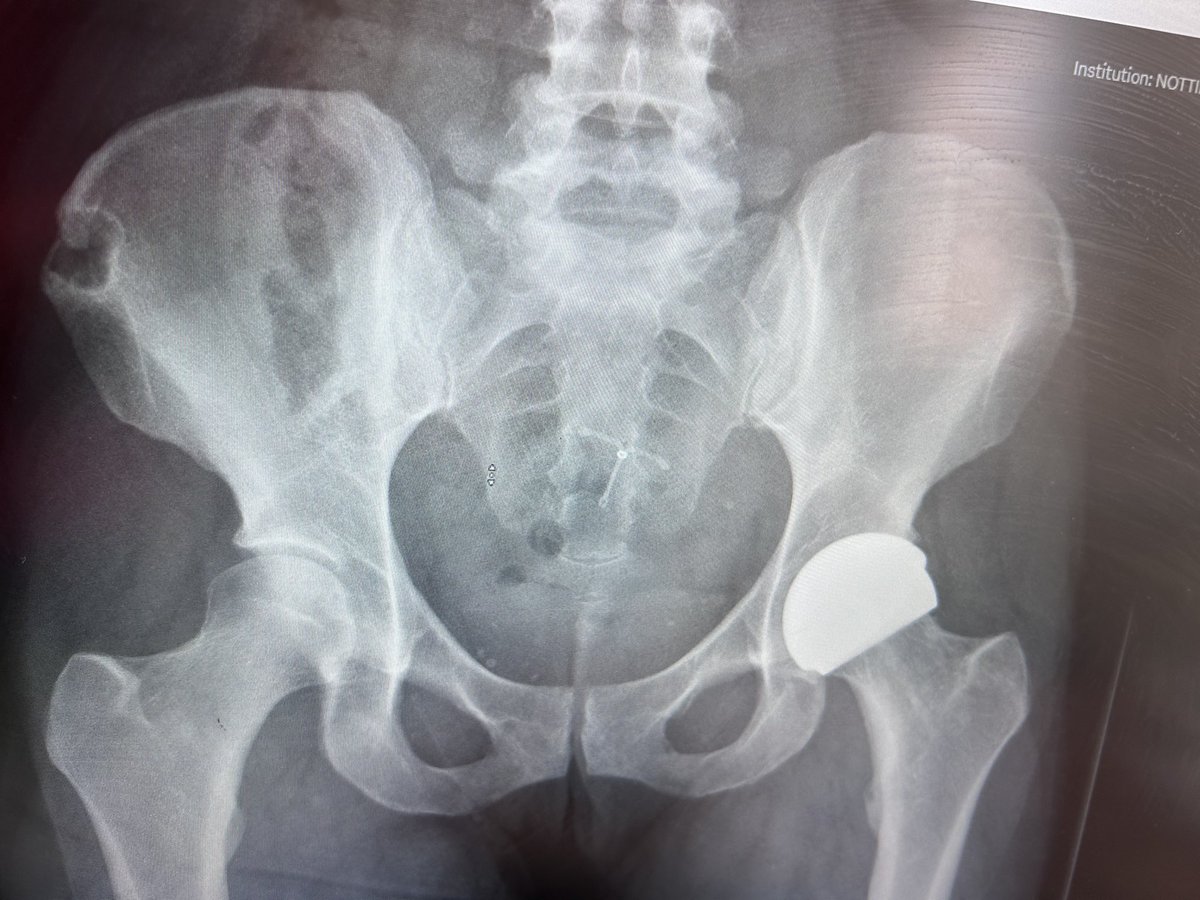

One year post operation …. Super grateful to this amazing surgeon Mr Andrew Manktelow and his team… i am so fortunate to be given a hip resurface as part of his hip replacement study.. #grateful #secondchance ❤️💪🙏 Ceramic hip resurfaces are the way forward!@AndrewManktelow

One year post operation ….

Super grateful to this amazing surgeon Mr Andrew Manktelow and his team… i am so fortunate to be given a hip resurface as part of his hip replacement study..  #grateful #secondchance ❤️💪🙏 Ceramic hip resurfaces are the way forward!@AndrewManktelow